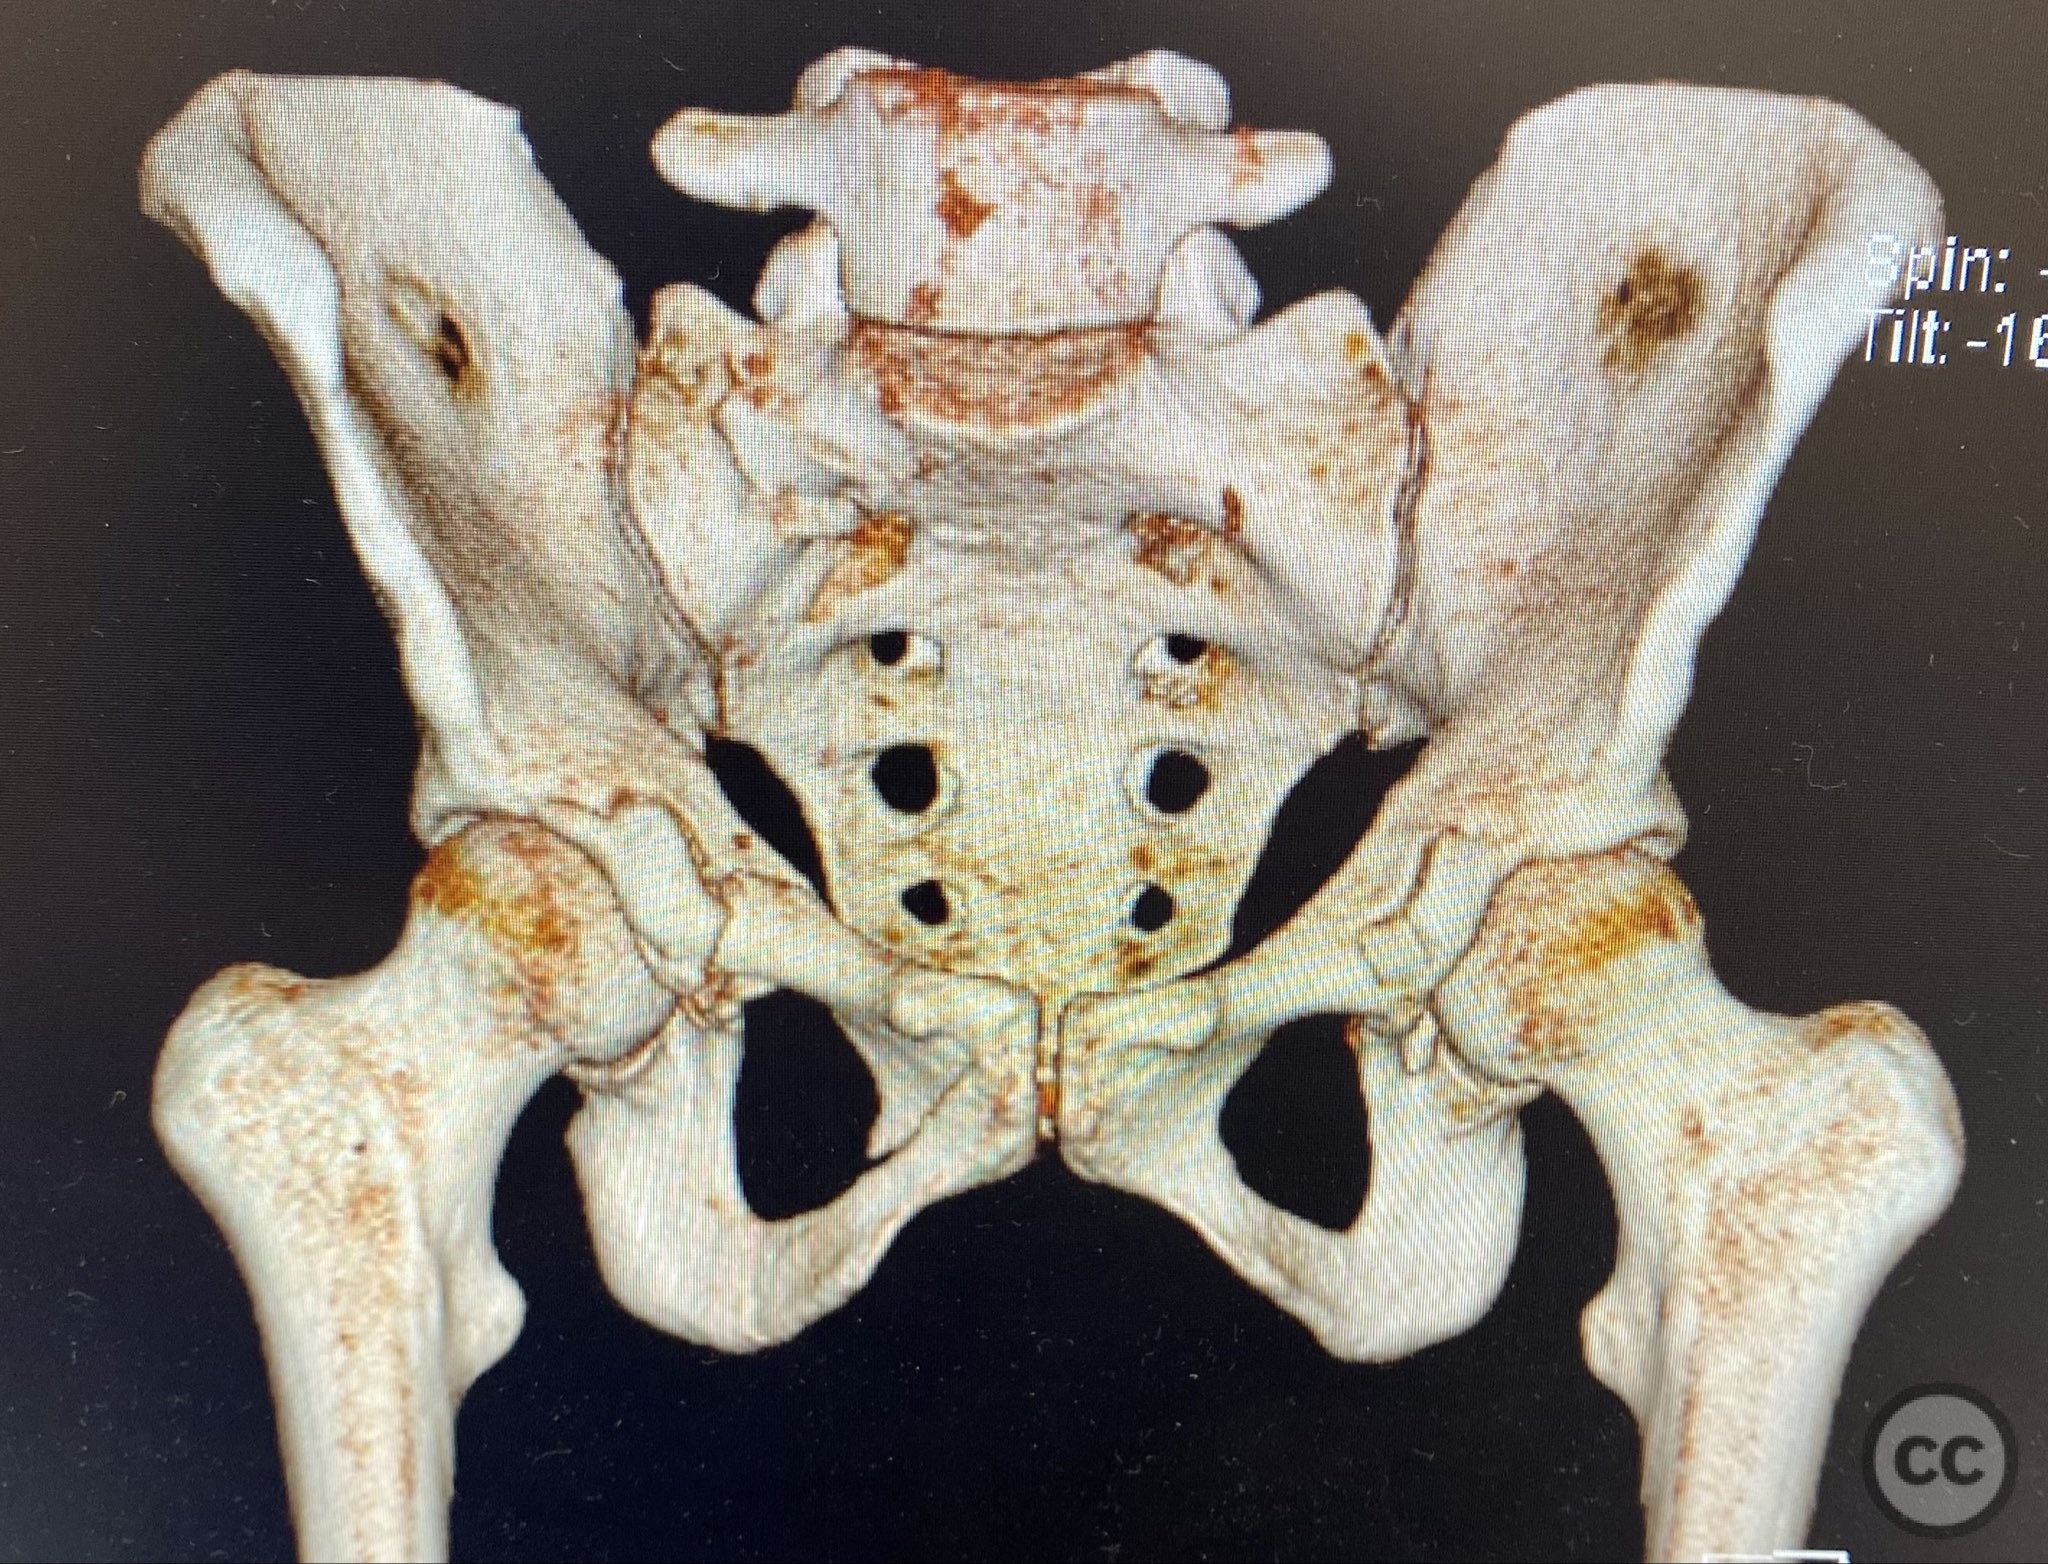

Clinical and radiological findings:  A middle-aged patient involved in a motor vehicle collision presented initially with a closed ankle fracture-dislocation and minimal pelvic complaints. Following closed reduction and splinting of the ankle, the patient developed severe pelvic pain (9/10) with any attempted movement. Neurological and vascular examination was not specified. Computed tomography demonstrated minimally displaced fractures of the posterior ilium, sacral ala, and bilateral pubic rami. AP CT surface renderings revealed subtle but clinically significant displacement and deformity of the pelvic ring, which was difficult to appreciate on standard axial images.